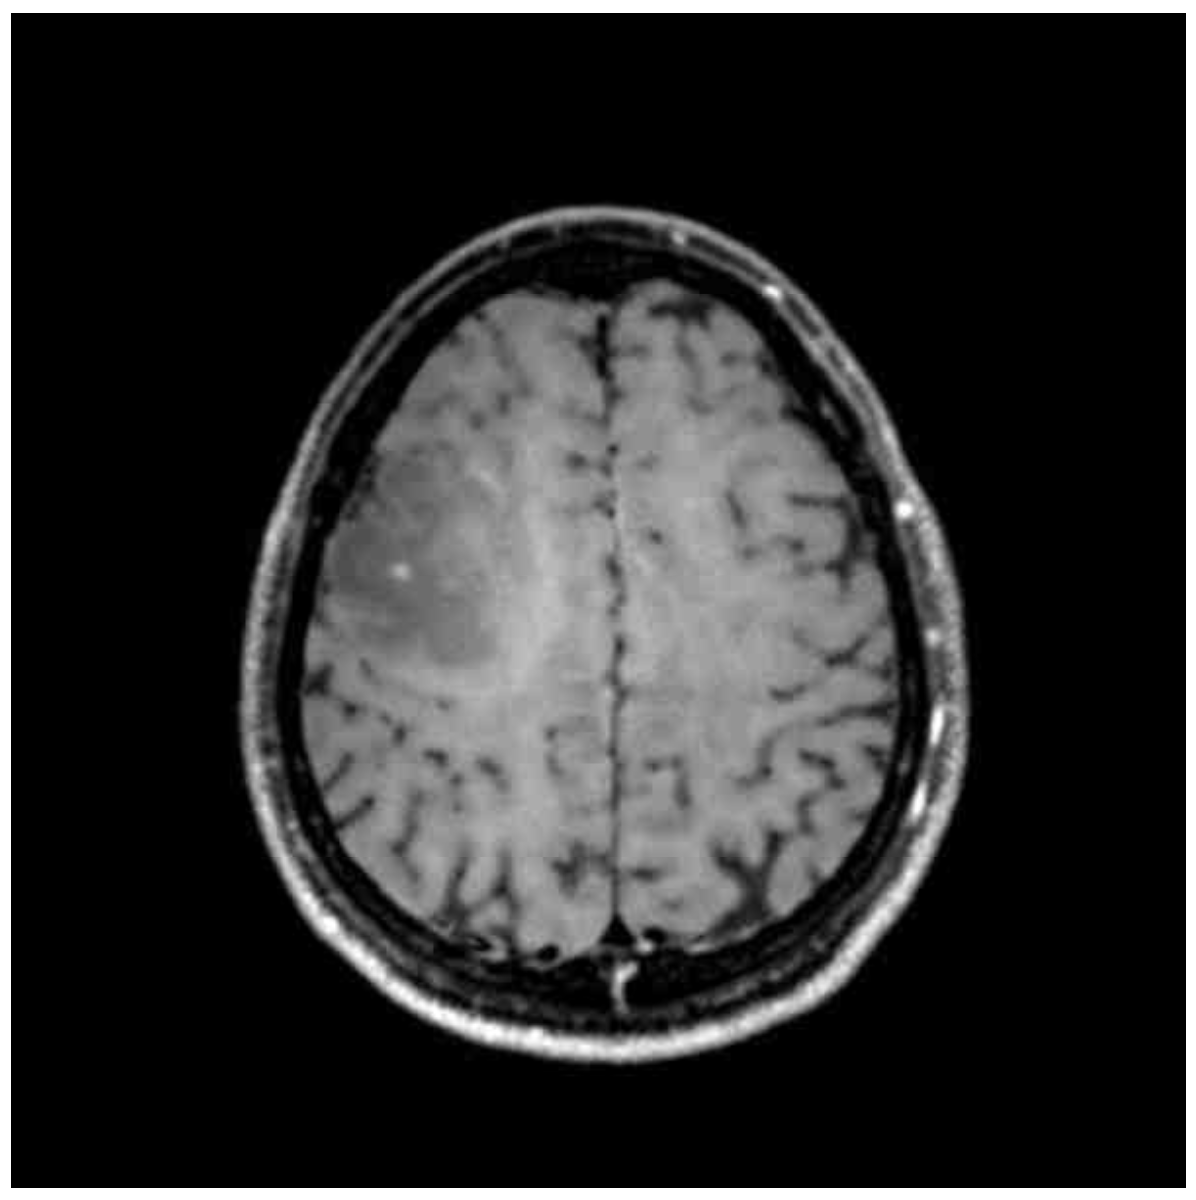

Img | MRI: T1WI hypointense, T2WI hyperintense Rt. frontoparietal mass |

T2-weighted brain MRI에서 hyperintense mass, T1-weighted brain MRI에서 hypointense mass가 확인되므로 뇌종양으로 진단한다.

• 뇌 영상검사 상 T2-weighted brain MRI에서 hyperintense mass, T1-weighted brain MRI에서 hypointense mass가 확인되므로 뇌종양으로 진단한다.

① T1WI: 저음영 종양 (지방 고음영, 물 저음영)